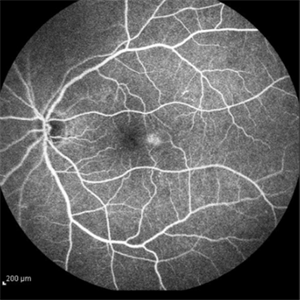

Idiopathic Juxtafoveal Telangiectasia, Type 2

Nov 6 2014 by Thomas A. Ciulla, MD, MBA, FASRS

Note the telangiectactic vessels just temporal to the FAZ.

Photographer: Thomas Steele

Condition/keywords: idiopathic macular telangiectasia, juxtafoveal telangiectasis, parafoveal telangiectasia